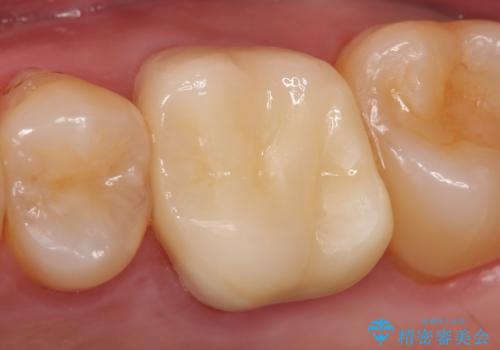

結合組織の追加移植

1次手術により唇舌的ボリュームはかなり改善されたが、前方面観による歯根の露出がまだ目立ったため、チタンメッシュの除去と同時に追加の結合組織移植をおこなった。